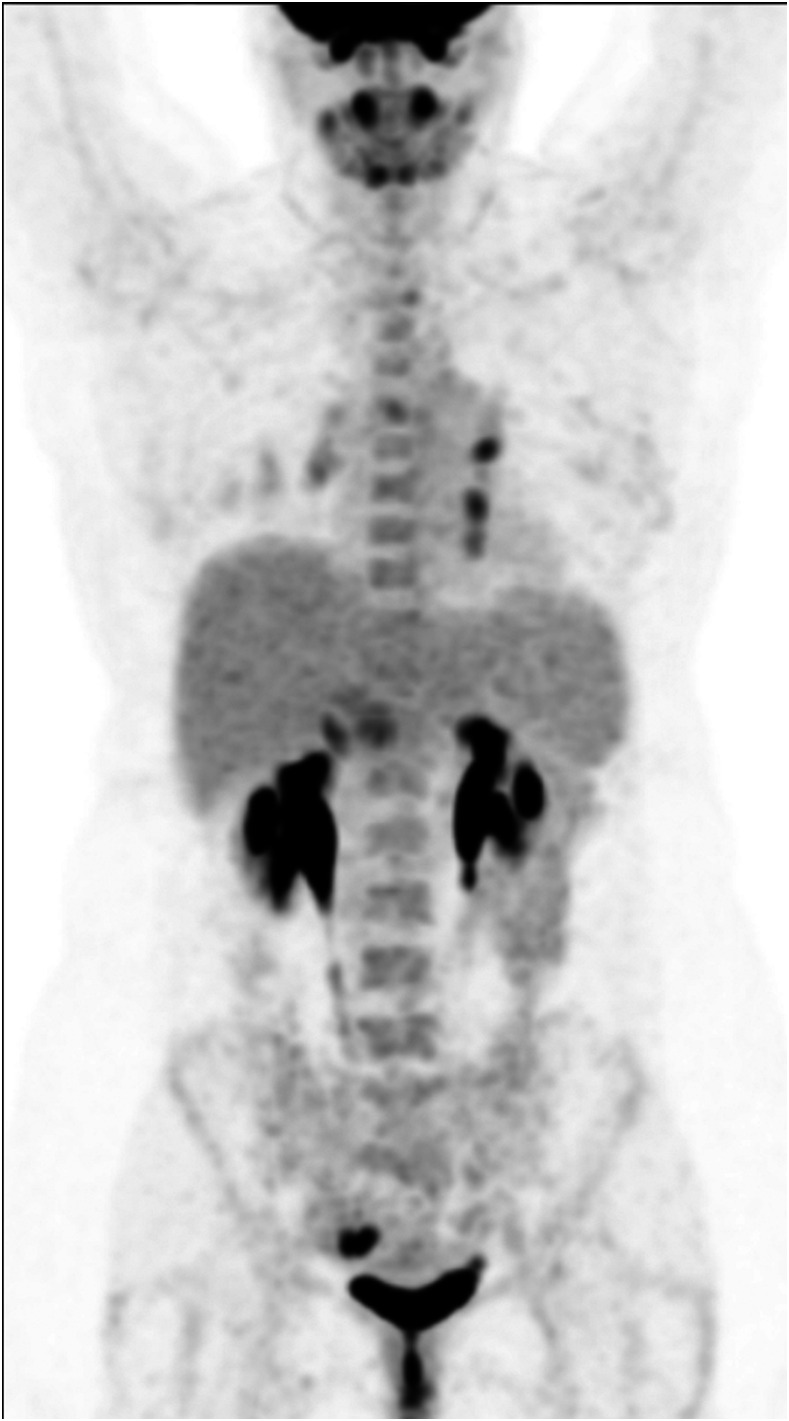

Figure 1.

Maximum intensity projection image of position emission tomography.